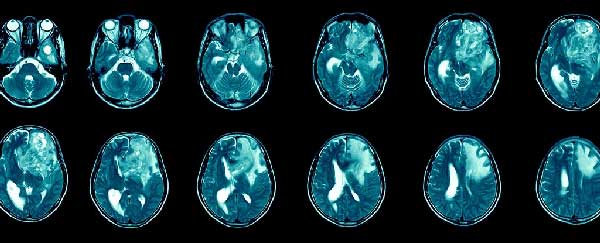

نوعی هیدروژل جدید که تا این مرحله روی موشها آزمایش شده است و نتایج آن در نشریه علمی معتبر PNAS منتشر شده است، موفق به پاکسازی آثار تومورهای گلیوبلاستوما شده و از بازگشت آنها جلوگیری کرده است.

این هیدروژل به قدری مؤثر بوده که نرخ زنده ماندن 100 درصدی که نرخ فوقالعادهای در این نوع سرطان به شمار میرود را در حیوانات به همراه داشته است.

در مرکز این ژل که به صورت ساختارهای رشتهای در مقیاس نانو برای ورود به مغز آماده شده است، از پاکلیتاکسل که نوعی داروی شیمیدرمانی است استفاده شده است. این دارو پیش از این برای درمان سایر سرطانها از جمله سرطان پستان و ریه تأییدیه دریافت کرده است. در مورد تومورهای مغزی، نحوه رساندن دارو به سلولهای سرطانی، کلیدیترین مرحله کار است.

این هیدروژل، پس از عمل جراحی برداشتن تومور سرطانی، حفره سرطانی و شیارهای نازکی که در اثر برداشتن تومور به جا میماند را به طور یکنواخت میپوشاند و طی چند هفته آنتیبادی به نام aCD47 آزاد میکند. به نظر میرسد که این روش درمانی به قسمتهایی از محل تومور دسترسی پیدا میکند که سایر داروها نمیتوانند به آنجا برسند.